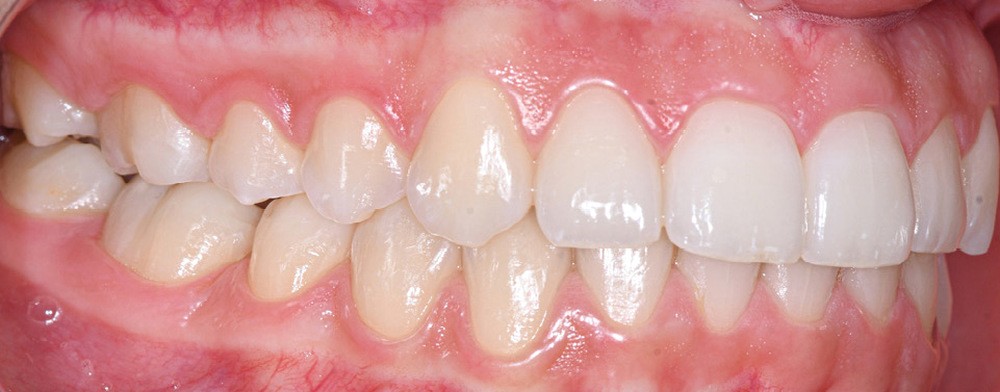

Nous détaillons la technique à travers le cas d’une jeune fille de 18 ans présentant des lésions carieuses sur quatre dents (fig. 1 à 14).